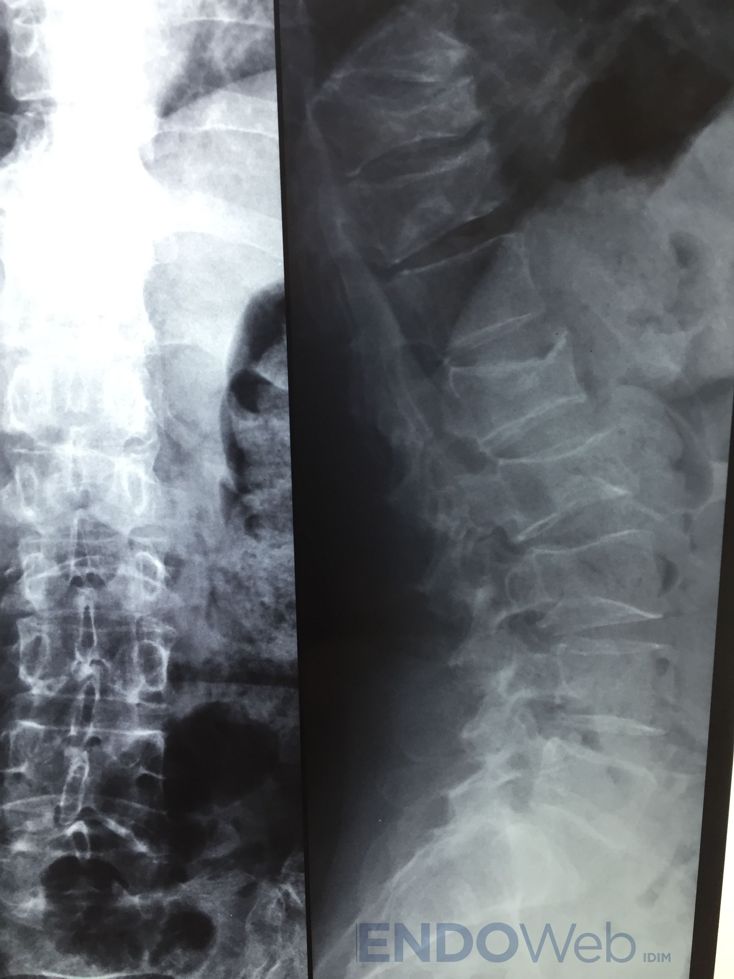

Se solicitó radiografía de columna dorso-lumbar:

Disminución altura vertebral cuerpos vertebras dorsales: D5, D8, D10 y D11. Biconcavidad vértebras lumbares L1 L2 L3